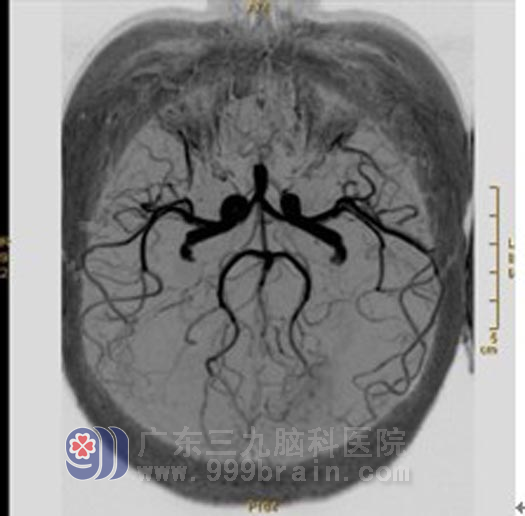

X-刀治疗半年后:原左顶叶病灶内流空信号异常血管已消失;左顶叶畸形血管团较前明显缩小,左大脑中动脉远端较前稍变细。